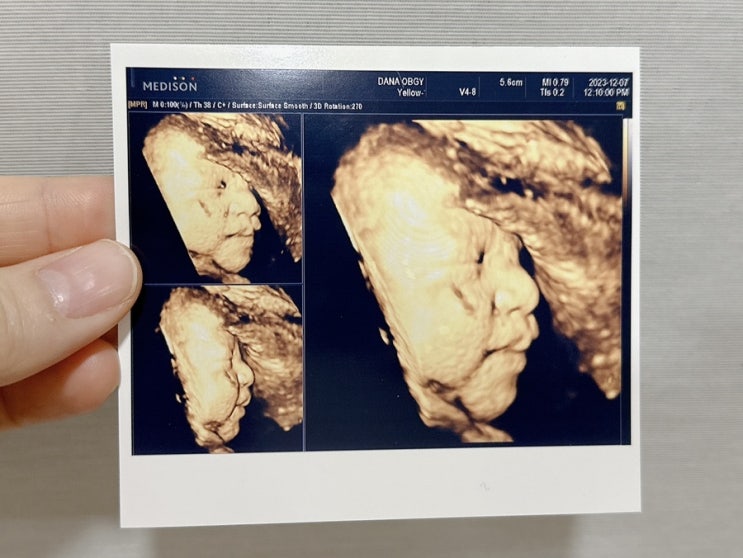

[임신기록] 임신 34~37주, 막달 검사, 수술전검사, 태동 검사, 마지막 초음파 진료

임신34주 막달 검사, 수술전검사 둘째 임신 34주 차 막달 검사 수술전검사가 있어 산부인과를 방문했다. 검...